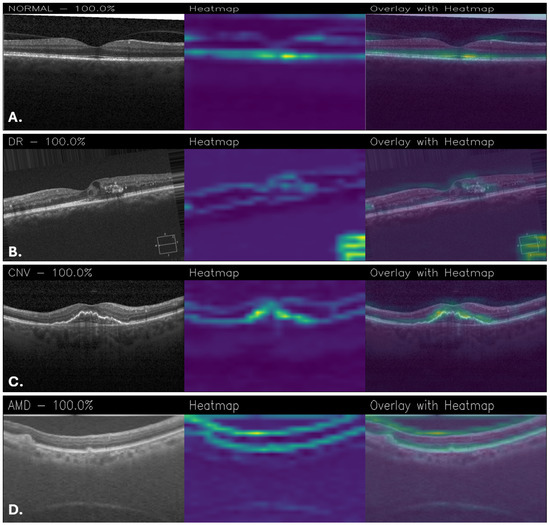

Figure 12 shows Grad-CAM visualizations of OCT images classified by the proposed MobileNetFT, highlighting the image regions most influential for the model’s decisions. For the healthy retina (Figure 12A), the activation is uniformly low across the retinal layers, with no focal areas of high importance, consistent with the absence of localized pathology. In DR (Figure 12B), the model emphasizes regions with hyperreflective lesions and retinal thickening, although some areas of the heatmap appear noisy. For CNV (Figure 12C), the central subretinal area corresponding to structural disruption shows the strongest activation. In AMD (Figure 12D), the heatmap highlights the outer retinal layers, particularly areas of drusen-like elevation and irregularity. However, the activations appear to be widely distributed, without focusing on specific details, as shown in Figure 12. This suggests that the model bases its decisions on general patterns rather than well-defined details, which may be beneficial to the robustness of the model but at the same time may limit its ability to recognize very fine details within the images.

Figure 12. Grad-CAM visualizations obtained with the MobileNetFT for healthy retina (A), DR (B), CNV (C), and AMD (D).